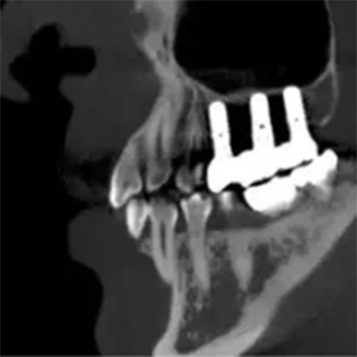

T-MAR Metal Artifact Reduction

T-MAR Metal Artifact Reduction in LargeV Dental CBCT

With the new T-MAR module, the system automatically removes metal artifacts and corrects image distortions intelligently.

Hence, the final images remain clear, accurate, and clinically reliable.